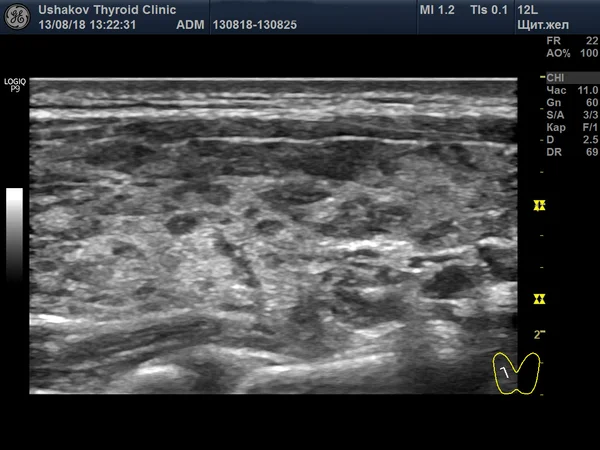

Снимок, сделанный через 10 месяцев, показывает значительное восстановление здоровой ткани железы.